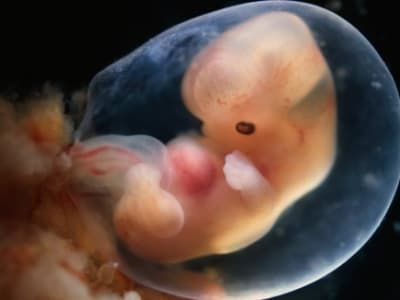

Video memperlihatkan bahwa embrio manusia tidak hanya menempel, tapi juga menarik dan menembus lapisan gel, mirip dengan proses menanamkan diri ke dalam rahim pada saat implantasi. Tindakan ini terjadi sangat cepat dan dinamis, berbeda dengan model tikus yang hanya menempel di permukaan.

Penelitian ini memberikan wawasan baru tentang proses biologis yang rumit dan tersembunyi dari awal kehamilan manusia. Temuan ini sangat berguna untuk memahami masalah reproduksi, seperti mengapa beberapa kehamilan gagal terjadi pada tahap awal implantasi.